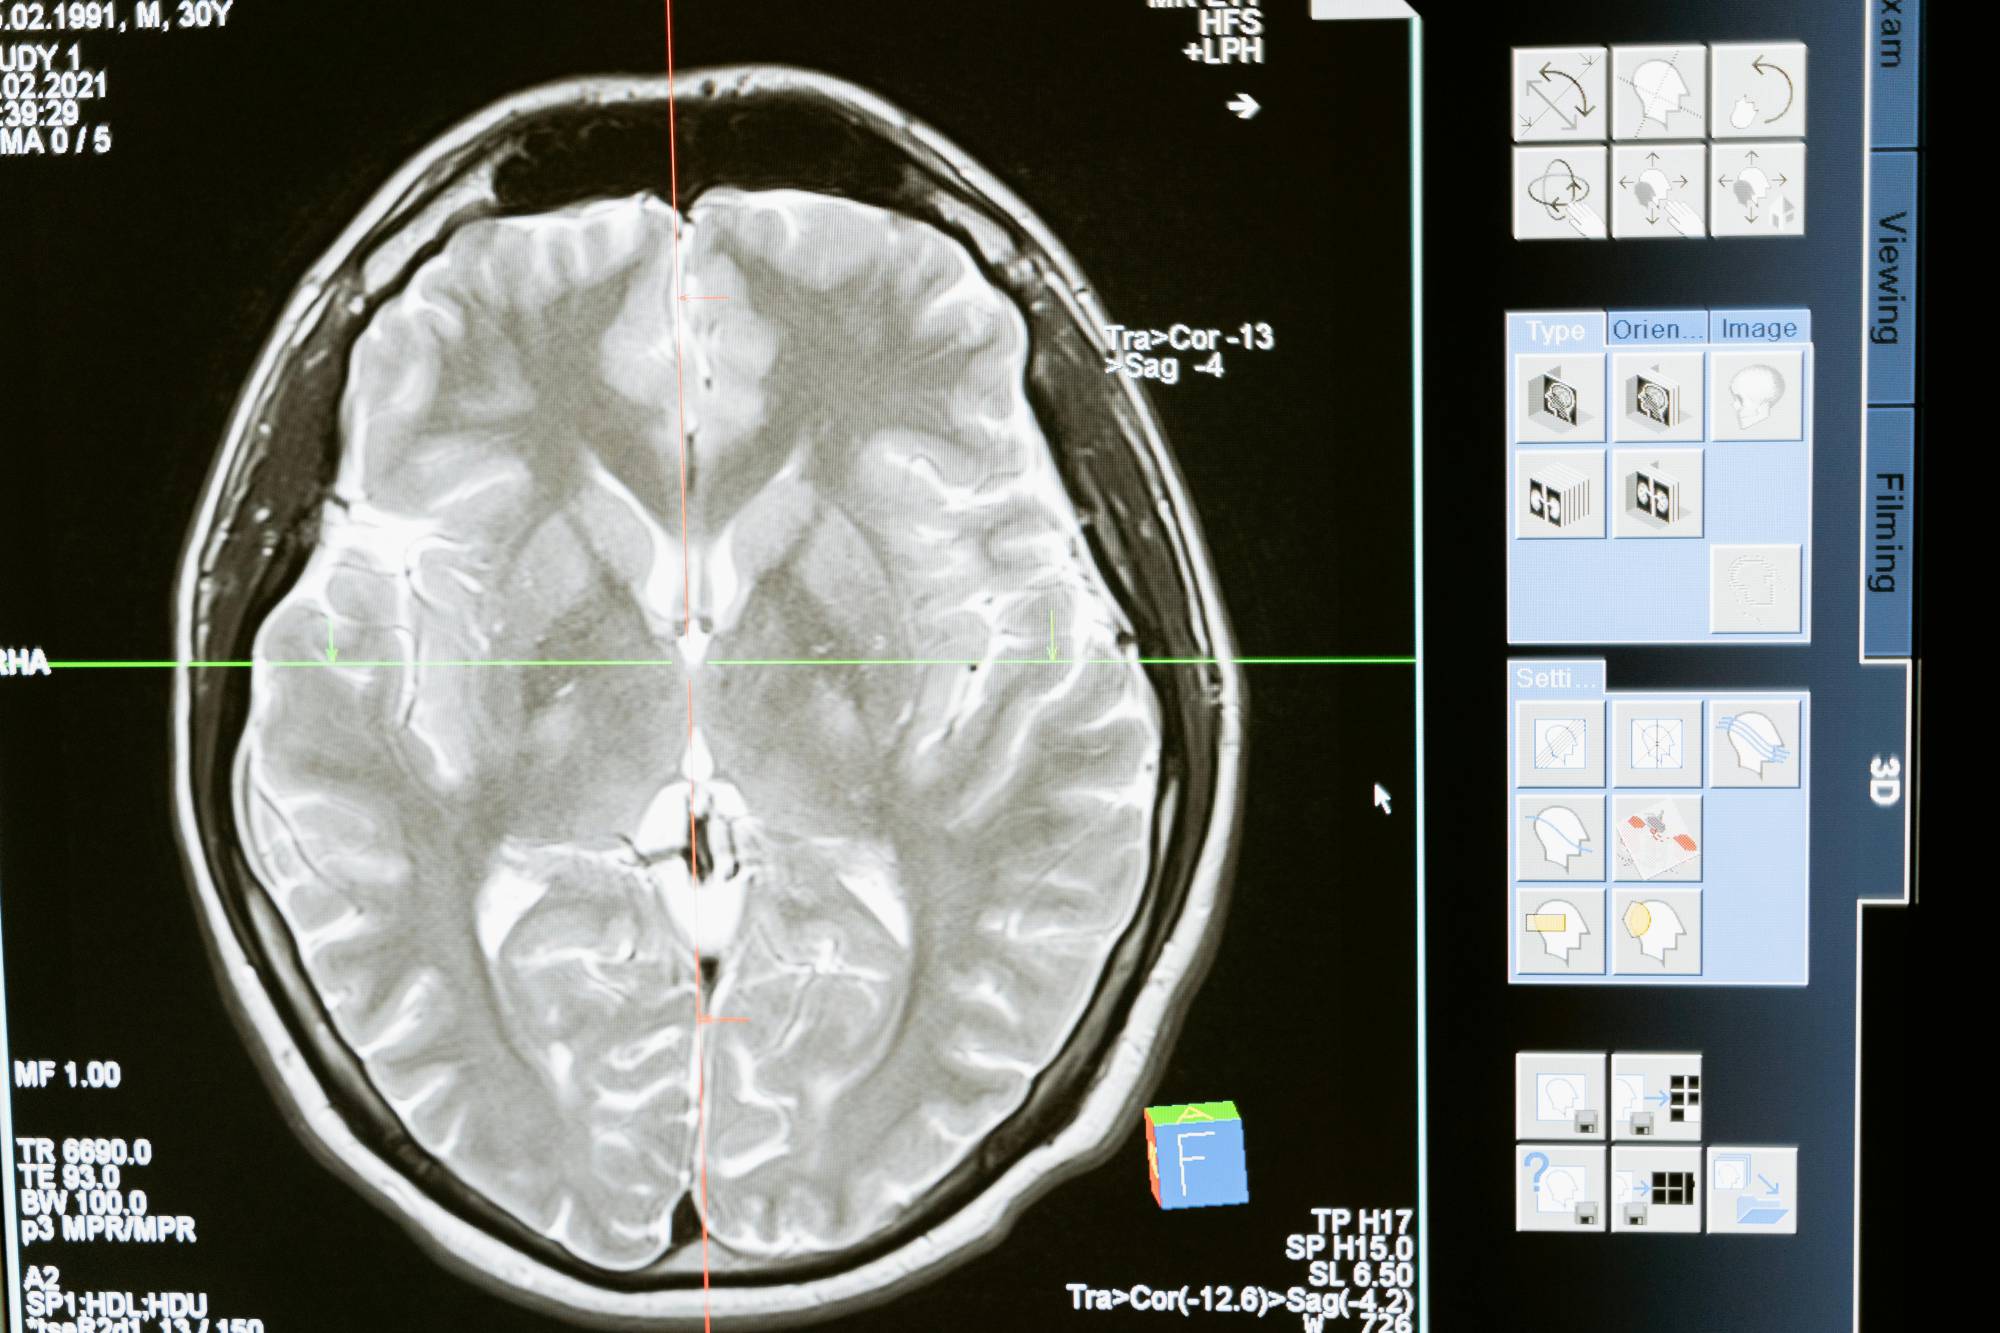

Alzheimer, la PET anticipa la diagnosi: funziona anche quando i test cognitivi non rivelano nessun declino

Utilizzando la PET, i ricercatori del Mass General Brigham di Boston hanno scoperto che il livello di declino cognitivo percepito dalla persona, finora ritenuto ‘non misurabile’, si associa all'accumulo di grovigli di proteina tau, un segno distintivo della malattia di Alzheimer